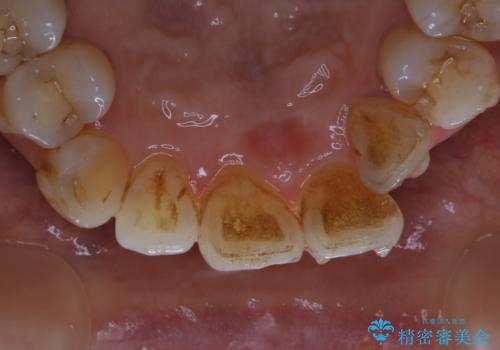

インビザラインの治療中の患者様のクリーニング前後写真です。

- インビザラインの矯正治療中に歯石や着色(ステイン)が付着してしまっていたため、歯科衛生士による専門的クリーニングを行いました。

今回はお口全体に歯石や着色(ステイン)が付着していたため、自費のPMTC(クリーニング)60分コースをご案内し、徹底的に除去しました。